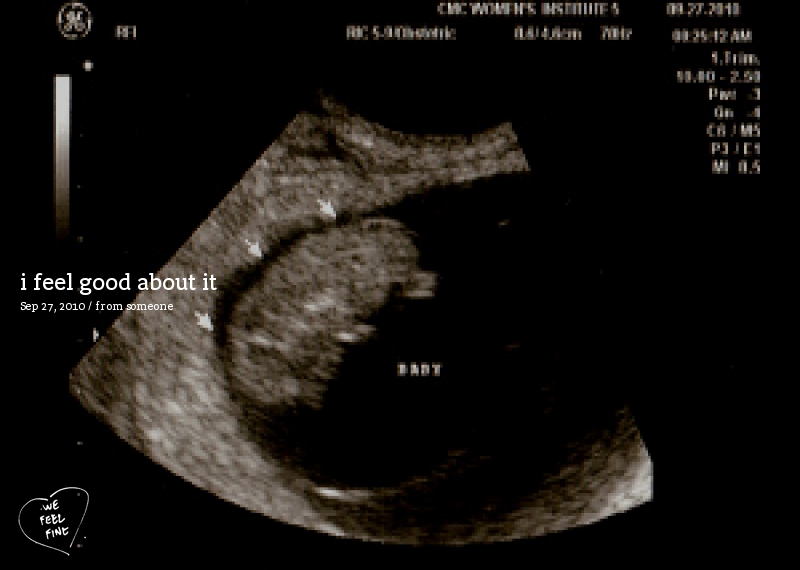

The original image can be seen here.